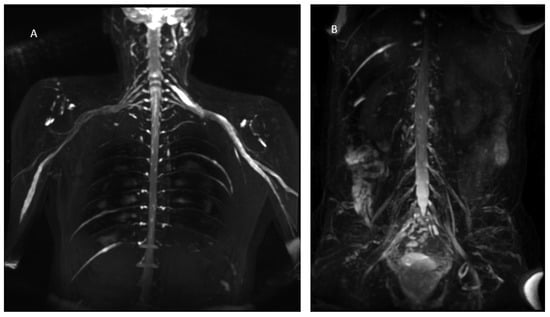

Figure 3.

MIP (Maximum Intensity Projection) reconstructions of the 3D cube nerve MR sequence of the brachial (A) and lumbosacral (B) plexus showing a pathological and asymmetric thickening and increase in T2 signal representation of them.